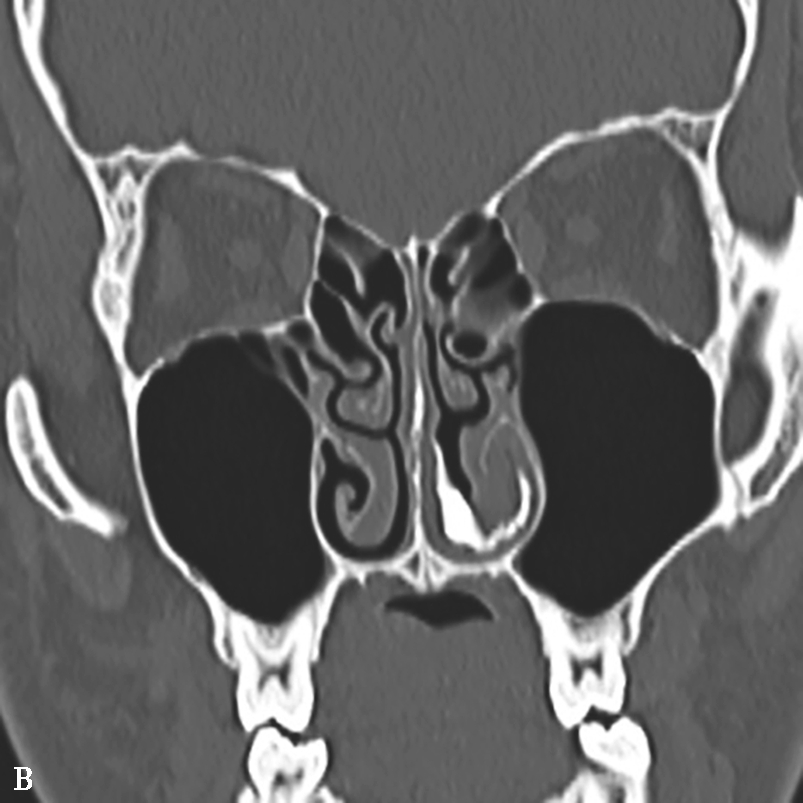

4.CT表现

①平扫表现:半组或全组窦腔内充填软组织影,骨窗示病变内部多发形态不一的云雾状或磨玻璃样密度影,CT值约100HU,软组织窗更为明显,呈不规则线状、匍匐状或斑片状高密度影(图1-3-22);常伴单或双侧鼻息肉;窦腔扩大、窦壁变薄、骨质吸收或结构不清,筛窦最常受累,眶纸板最常见骨质吸收,眶内侵犯多见。②增强扫描表现:边缘黏膜明显强化。

图1-3-22 变应性真菌性鼻窦炎

A、B.横断面、冠状面CT骨窗,示双侧上颌窦、筛窦腔膨胀,窦腔充填软组织密度影,病变内部可见片状磨玻璃样密度增高影,上颌窦壁骨质增生硬化;C.横断面CT软组织窗,示病变内部磨玻璃样密度影显示更清楚

5.MRI表现

①T 1 WI表现:呈低或等信号,外周阻塞炎症多呈低信号。②T 2 WI表现:呈低或极低信号,外周阻塞炎症多呈高信号。③增强扫描表现:病变不强化,增强后外周阻塞炎症周边黏膜明显强化。